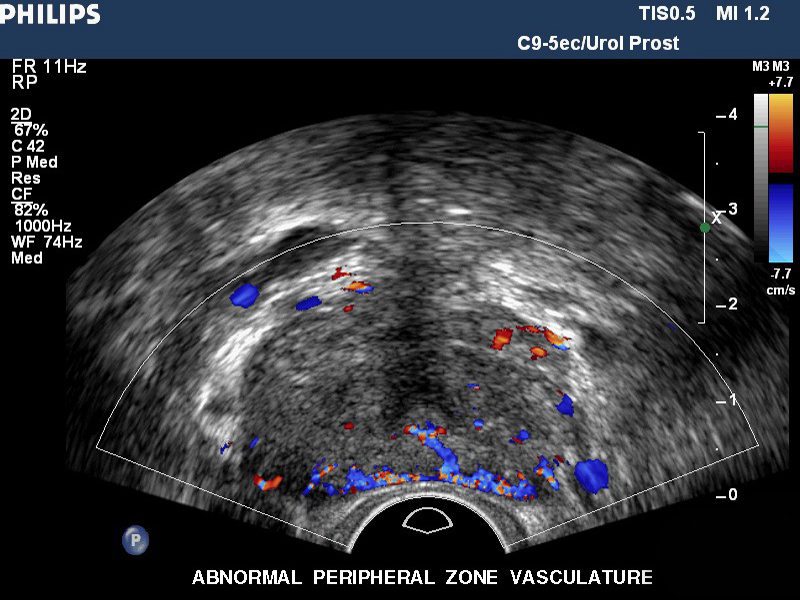

Ultrasonido prostático

Ultrasonido doppler